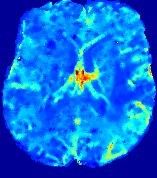

TimeSlice(i)(ii)(iii)(iv)(v)(vi)Refer to caption00555101010151515202020252525Refer to caption(a)(b)Refer to captionRefer to captionRefer to captionRefer to captionRefer to captionRefer to captionRefer to captionRefer to captionRefer to captionRefer to captionRefer to captionRefer to captionRefer to captionRefer to captionRefer to captionRefer to captionRefer to captionRefer to caption(a)(b)Refer to captionRefer to captionRefer to captionRefer to captionRefer to captionRefer to captionRefer to captionRefer to captionRefer to captionRefer to captionRefer to captionRefer to captionRefer to captionRefer to captionRefer to captionRefer to captionRefer to captionRefer to caption(a)(b)Refer to captionRefer to captionRefer to captionRefer to captionRefer to captionRefer to captionRefer to captionRefer to captionRefer to captionRefer to captionRefer to captionRefer to captionRefer to captionRefer to captionRefer to captionRefer to captionRefer to captionRefer to caption(a)(b)Refer to captionRefer to captionRefer to captionRefer to captionRefer to captionRefer to captionRefer to captionRefer to captionRefer to captionRefer to captionRefer to captionRefer to captionRefer to captionRefer to captionRefer to captionRefer to captionRefer to captionRefer to caption(a)(b)Refer to captionRefer to captionRefer to captionRefer to captionRefer to captionRefer to captionRefer to captionRefer to captionRefer to captionRefer to captionRefer to captionRefer to captionRefer to captionRefer to captionRefer to captionRefer to captionRefer to captionRefer to caption(a)(b)Refer to captionRefer to captionRefer to captionRefer to captionRefer to captionRefer to captionRefer to captionRefer to captionRefer to captionRefer to captionRefer to captionRefer to captionRefer to captionRefer to captionRefer to captionRefer to captionRefer to captionRefer to caption

Figure 6: Predicted concentration time series for the same patient shown in Fig. 4, where (i)-(vi) correspond to slices #1-6 respectively. Each grouped row displays (a) the measured concentration image sequences and (b) the predicted concentrations at corresponding time points.

3.2 Predicted CA Concentration

To better illustrate the prediction accuracy, and therefore the estimation accuracy of 𝐕𝐕{\bf V} and D𝐷{D}, of PIANO, we provide the corresponding predicted time-series of CA concentration images in Fig. 5 and Fig. 6 for the same patients in Fig. 3 and Fig. 4, respectively. We see that PIANO is capable of predicting the CA concentration given their initial state, indicating its ability to successfully capture 𝐕𝐕{\bf V} and D𝐷{D}. Note that although the concentration values for these two patients differ considerably, caused by the different total volume of injected CA, PIANO is still able to provide plausible estimates.